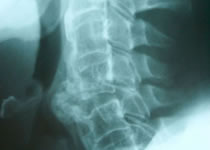

Radiología

Interpretación de estudios de imagen: